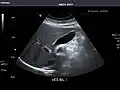

Liver

Ultrasonography of the liver with some standard measurements[6]

In patients with deranged liver function tests, ultrasound may show increased liver size (hepatomegaly), increased reflectiveness (which might, for example, indicate cholestasis), gallbladder or bile duct diseases, or a tumor in the liver.

Ultrasonography of liver tumors involves two stages: detection and characterization. Tumor detection is based on the performance of the method and should include morphometric information (three axes dimensions, volume) and topographic information (number, location specifying liver segment and lobe/lobes). The specification of these data is important for staging liver tumors and prognosis. Tumor characterization is a complex process based on a sum of criteria leading towards tumor nature definition. Often, other diagnostic procedures, especially interventional ones, are no longer necessary. Tumor characterization using the ultrasound method will be based on the following elements: consistency (solid, liquid, mixed), echogenicity, structure appearance (homogeneous or heterogeneous), delineation from adjacent liver parenchyma (capsular, imprecise), elasticity, posterior acoustic enhancement effect, the relation with neighboring organs or structures (displacement, invasion), vasculature (presence and characteristics on Doppler ultrasonography and contrast-enhanced ultrasound (CEUS).